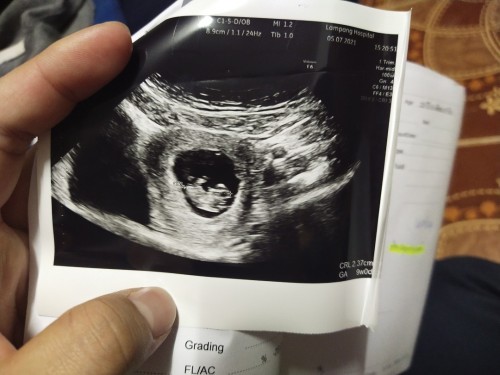

แม่บ้านนี้อัลตร้าซาวด์ฝากครรภ์ตอนอายุครรภ์ 7 สัปดาห์ เจอตัวอ่อนจ๊ะ

ตอน8สัปดาห์5วันคะคุณแม่ เจอตัวเเละหัวใจ6สัปดาห์คะ